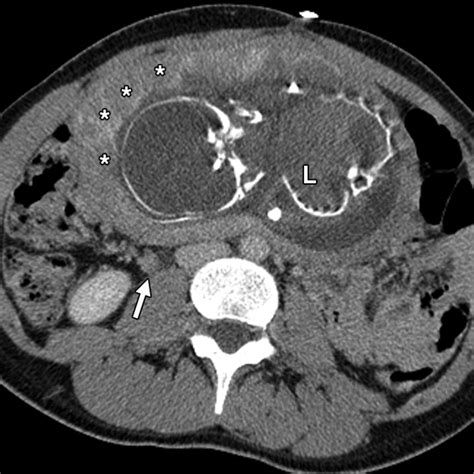

Radiation Dose and Fetal Risk

The risk to the fetus depends on the radiation dose and the stage of pregnancy. The following table provides a general guideline on the radiation doses from common CT scans and the associated risks:

CT Scan Type Approximate Radiation Dose (mGy) Fetal Risk

Head CT 0.01-0.05 Low

Chest CT 0.01-0.05 Low

Abdomen/Pelvis CT 5-10 Moderate

Full-Body CT 10-20 High

It is important to note that the radiation dose from a single CT scan is typically below the threshold that would cause immediate harm to the fetus. However, repeated or high-dose scans can increase the risk of long-term effects, such as childhood cancer.